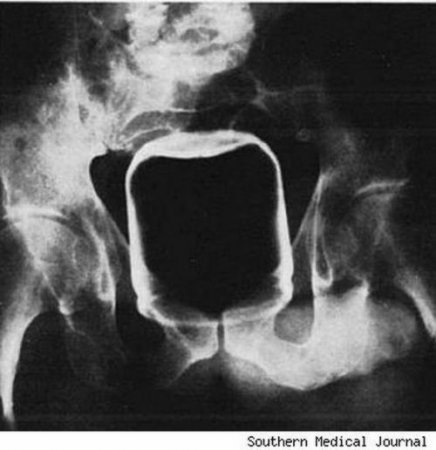

Без комментариев.